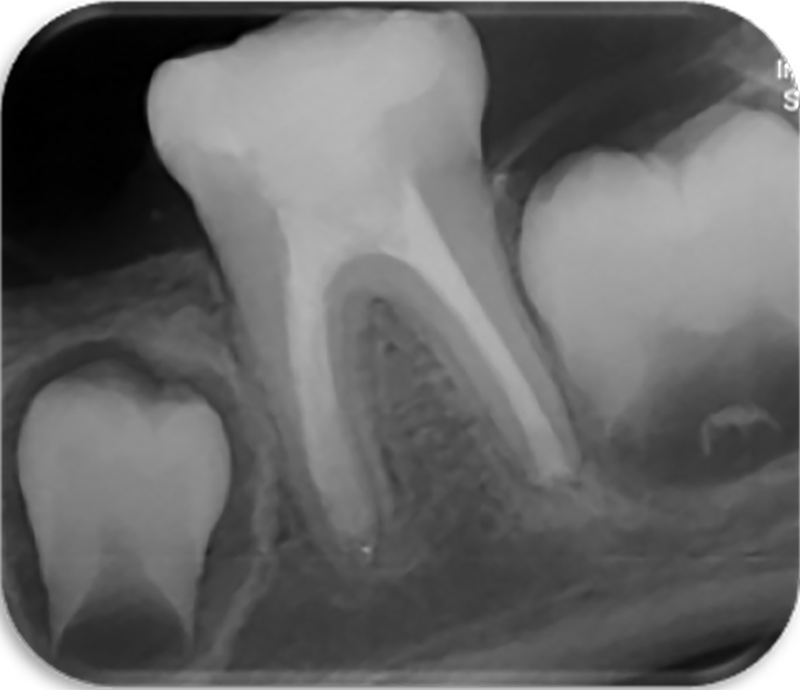

مشاهده موارد درمان شده به بیماران اطمینان میدهد که حتی دندانهای آسیبدیده و پیچیده نیز با درمان تخصصی قابل حفظ هستند. همچنین این بخش فرصتی برای همکاران دندانپزشک فراهم میکند تا با روند و نتایج درمانهای پیچیده آشنا شوند.

تشخیص دقیق و درمان استاندارد در اندودنتیکس بدون بهرهگیری از تکنولوژیهای روز دنیا امکانپذیر نیست. در این مرکز مجموعهای از تجهیزات مدرن بهکار گرفته شده است تا درمان در محیطی ایمن، کمدرد و با بالاترین دقت انجام شود. یکی از این امکانات، رادیوگرافی دیجیتال با دوز بسیار پایین اشعه است. این فناوری نسبت به رادیوگرافیهای قدیمی میزان اشعه را تا حد قابلتوجهی کاهش میدهد، در عین حال تصویری بسیار واضح و دقیق ارائه میکند. تصاویر دیجیتال بلافاصله قابل مشاهده هستند و امکان بزرگنمایی، بررسی ضایعات و ارزیابی طول کانال با دقت بالا را فراهم میکنند. برای بیمارانی که نگران درد تزریق هستند، بیحسی دیجیتال یک گزینه مناسب است؛ سیستمی که تزریق آن با کنترل کامپیوتری انجام میشود و به دلیل تنظیم دقیق فشار و حجم تزریق، یکی از کمدردترین روشهای بیحسی محسوب میشود. این تکنولوژی بهویژه برای بیماران مضطرب یا دندانهای با التهاب بالا بسیار مؤثر است. برای مرحله پرکردن کانال، از روش ترموپلاستیک سهبعدی استفاده میکنیم تا سیل دقیقتری در کانالها و انشعابات فرعی ایجاد شود. همچنین تمامی محلولهای شستشو با سیستمهای سونیک و اولتراسونیک فعالسازی میشوند؛ روشی که اثربخشی شستشو را چند برابر میکند و باعث حذف کاملتر باکتریها و دبریها میشود. این تکنولوژیها سهم بزرگی در موفقیت نهایی درمان و ماندگاری آن در بلندمدت دارند. استفاده از میکروسکوپ دندانپزشکی، رادیوگرافی دیجیتال کمدوز، بیحسی دیجیتال، تکنیکهای گرم برای پرکردن کانال، فعالسازی پیشرفته محلولهای شستشو و بسیاری از امکانات و تجهیزات تخصصی دیگر باعث شده است که درمانهای اندودنتیک در مطب دکتر سلطانی نژاد با بالاترین استانداردهای جهانی، بیشترین دقت و کمترین ناراحتی برای بیمار انجام شود.